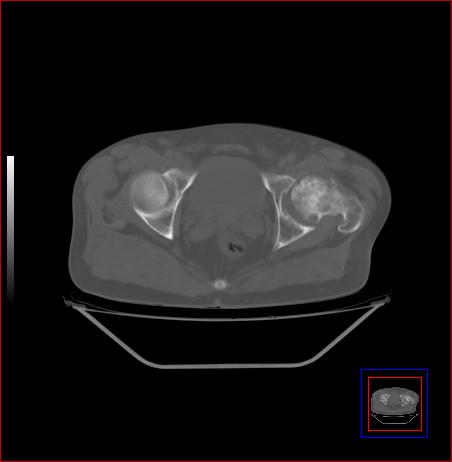

标题: CT15143:髋关节结核?

男,49,髋关节疼痛1年,无肺结核。

骨质破坏,硬化,周围软组织脓肿,关节间隙增宽,支持骨结核

骨质破坏,硬化,周围软组织脓肿,关节间隙增宽,支持骨结核 .应与无菌坏死鉴别

可以是结核,也可以是无菌坏死,还可以是先天髋关节脱位,不结合临床病史,只凭图像鉴别,请各位老师指教。